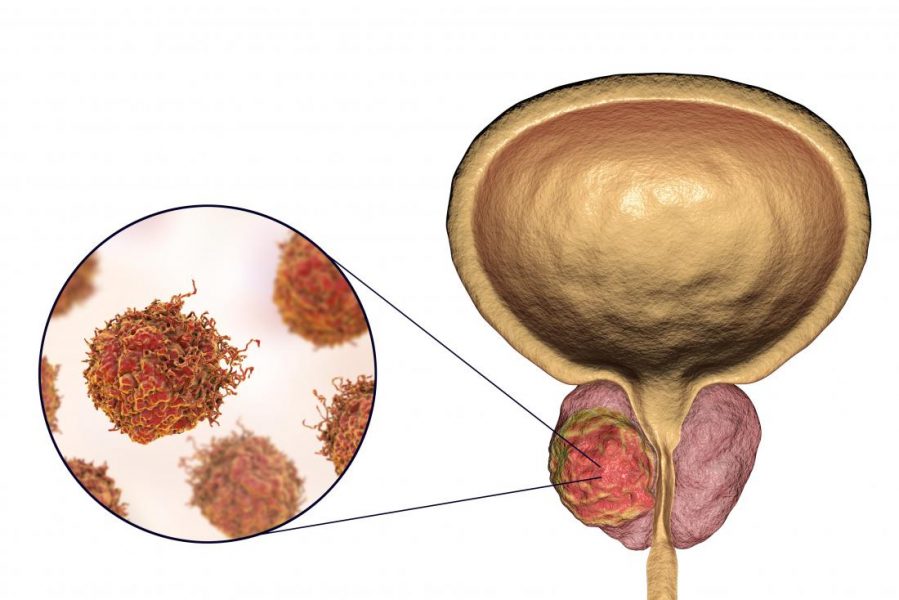

شیمیدرمانی نقش مهمی در مبارزه با سرطان دارد. این باعث تغییر مقادیر خونی بیمار میشود. به طور خاص، پلاکتها با شیمیدرمانی کم هستند. ارزش شما به زیر 120000 پلاکت در یک میکرولیتر خون میرسد. در این مورد، پزشکان از ترومبوسیتوپنی در طول شیمیدرمانی صحبت میکنند. اگر تعداد ترومبوسیتها به نام پلاکت کاهش یابد، ممکن است […]